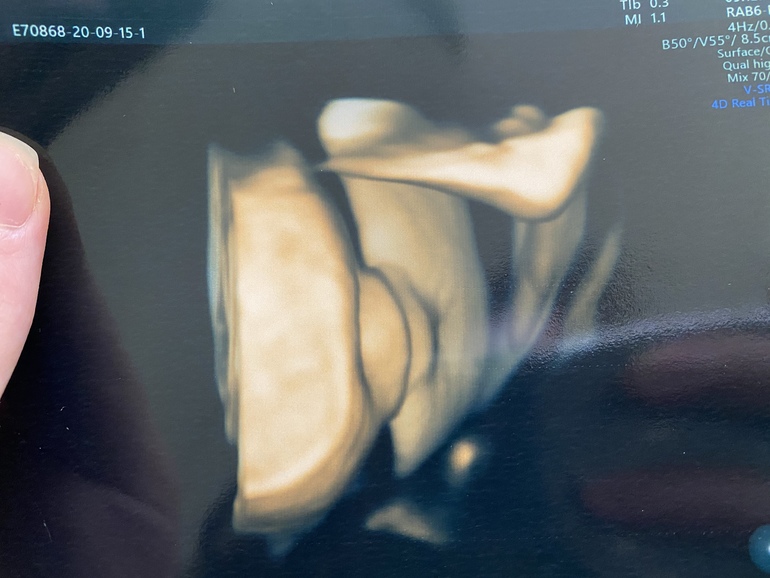

УЗИ, КТГ, доплерБыла сегодня на узи . Срок 38.3 и по месячным и по узи . Шейка 32 мм, зев сомкнут )степень зрелости Плаценты 2-3 ст . доча 3300 и 50 см . После узи пошла на осмотр к врачу . Шейка длинная , пропускает палец ) как долго я ещё буду хоть и есть ли шанс родить в пдр ?😄я уже отчаялась . Доче там видимо и так неплохо ) но ходить до 42 недель вообще нет никаких сил 😩